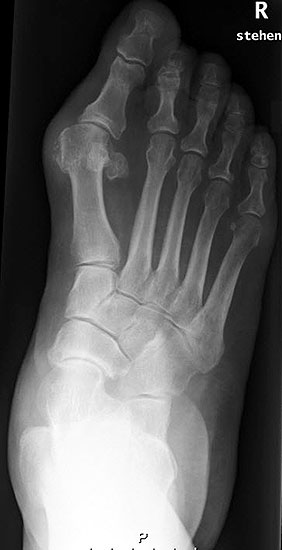

Stehende konventionelle Röntgenbilder eines Fußes mit Planovalgus Deformität Stadium II b dorsoplantar (dp) und seitlich. Auf der dp-Aufnahme zeigt sich die talo-calcaneare Divergenz, der gegenüber dem Kalkaneus nach anterior gleitende Talus und d

Abbildung 5

Stehende Aufnahmen des Fußes dorsoplantar (dp) und seitlich sowie des OSG anteroposterior (ap) sind die Grundlage der konventionellen Röntgendiagnostik (Abb. 5). Ergänzend werden gelegentlich die Rückfuβ-Alignement Aufnahme nach Saltzman 19 und Vergleichsaufnahmen der Gegenseite durchgeführt.

Der Talo-Metatarsale I Winkel bzw. die laterale talonaviculare Subluxation auf der stehenden dorsoplantaren Aufnahme des Fuβes dokumentieren das Ausmaβ des Vorfuβ abductus (Abb. 6 a,b). Ein dp Talo-Metatarsale I Winkel von > 10° (nach medial konvex) ist als pathologisch anzusehen. Mit der Bestimmung der talocalcanearen Divergenz (Abb. 6 c) erhält man ein Eindruck über das Ausmaβ des Rückfuβ valgus; eine leichte Divergenz bis ca. 12° gilt als physiologisch 20.

Auf der seitlichen, stehenden Aufnahme des Fußes wird ebenfalls der laterale Talo-Metatarsale I Winkel (Abb. 6 d) gemessen und so das kollabierte mediale Längsgewölbe dokumentiert. Auch hier gilt ein Talo-Metatarsale I Winkel von > 5° (nach plantar konvex) als pathologisch 21. Der Kollaps findet dabei meist im Talonaviculargelenk, seltener in der Naviculocuneiform-Gelenkreihe statt. Instabilität und Arthrose im 1. TMT sollten ausgeschlossen oder bei der Operationsplanung mit einbezogen werden. Weitere wichtige radiologische Messungen zur Beurteilung der Planovalgus-Statik und Progression der Deformität sind der laterale talo-calcaneare Winkel (Abb. 6 e) und der Abstand des Os cuneiforme-Unterrandes zum Untergrund (Abb. 6 f, Cuneiform height, 22. Eine anteriore Translation des Talus auf dem Kalkaneus findet man sowohl auf der ap, als auch auf der seitlichen Aufnahme des Fuβes mit Aufhebung der Cima-Linie.